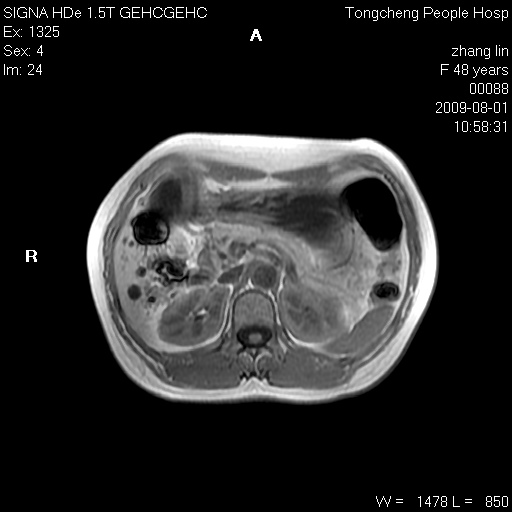

女,48岁。健康体检,彩超发现右肾占位性病变。平素健康。

临床诊断:右肾占位性病变,性质待定(囊肿?肿瘤?)。

上中腹部mr平扫+增强扫描,图像如下:

右肾上极见一类圆形病灶,t1wi呈等信号t2wi呈等高混杂信号,三期增强无强化,边界清---考虑囊肿出血。

同反相位均表现为等信号,病变无强化,考虑含蛋白的囊肿可能,弥散加权相或许有些帮助,